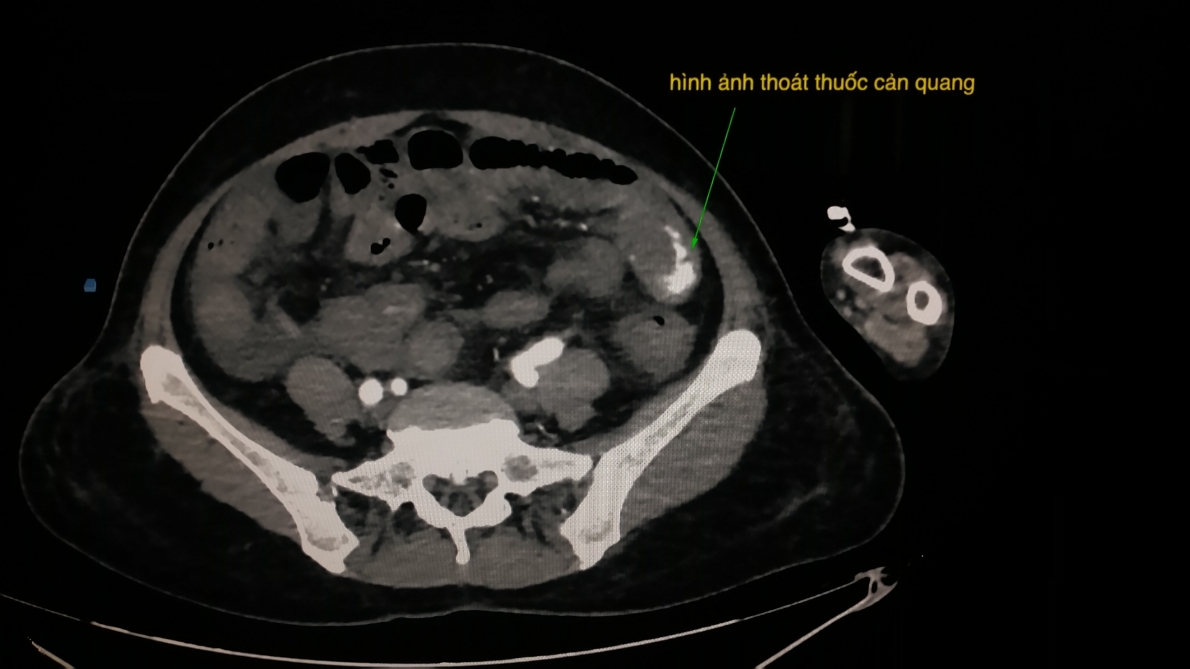

Ngay sau khi tiếp nhận, khoa Cấp cứu thực hiện qui trình báo động đỏ nội viện. Hội chẩn nhiều chuyên khoa thống nhất chẩn đoán: Choáng do xuất huyết tiêu hóa dưới nghĩ từ ruột non mức độ nặng - toan chuyển hóa - suy hô hấp, rối loạn đông máu. Bệnh nhân được tiến hành cấp cứu, truyền dịch, truyền máu, truyền huyết tương tươi đông lạnh khẩn cấp, hồi sức nội khoa, đặt nội khí quản, thở máy, chống toan, đặt catheter đo huyết áp động mạch xâm lấn. Kết quả kiếm tra ghi nhận bệnh nhân bị sốc mất máu nặng, chỉ số huyết học ở mức báo động: huyết sắc tố 4.0 g/dl (bình thường: 12.5 – 16g/dl). Thống nhất khi tình trạng bệnh nhân di chuyển được sẽ chụp cắt lớp vi tính bụng có cản quang trước để xem tình trạng thoát mạch. Kết quả ghi nhận hình ảnh thoát mạch thuốc cản quang trong thành quai ruột non hông trái, không thấy u bướu hay polyp.

Hình ảnh chụp cắt lớp vi tính bụng có cản quang ghi nhận có hiện tượng thoát thuốc cản quang